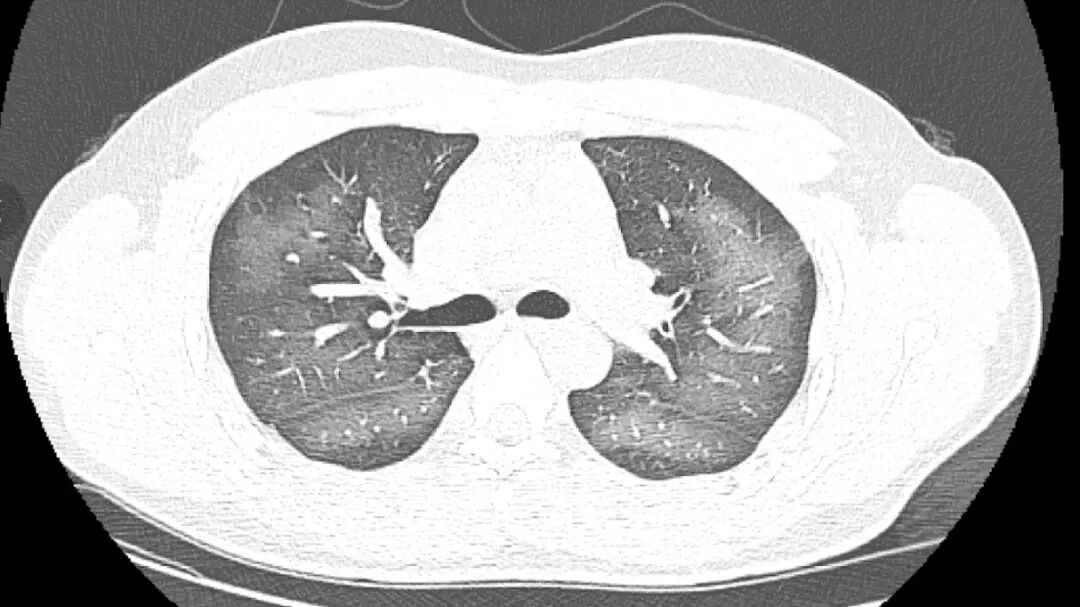

经检查,肺部计算机断层扫描检查(CT)结果显示,李林双肺赫然呈现大范围白色样病变,报告提示「白肺」。

据介绍,白肺一般是指重症肺炎在X光检查(X Ray)或CT检查下的表现,患者肺部呈现一大片的白色状态,往往会出现呼吸困难、呼吸衰竭,严重者还会出现其他脏器功能障碍。

长沙市第三医院放射影像科的接诊医生表示,除了感染、弥漫性肺泡出血综合症等白肺 最常见的病因外,吸入有害物质如粉尘、喷雾等,也可导致肺部出现大范围白色样病变。